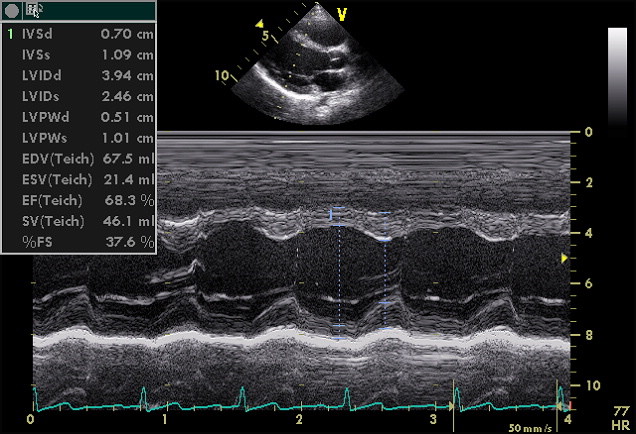

Echocardiography

Echocardiography (Echo) test uses sound waves to evaluate your heart. This test is painless and visualizes the heart without radiation providing the physician with valuable information about the function and structure of heart valves, heart muscle, and surrounding tissue (pericardium). The test is performed by an Echo Tech who stores the images digitally and then is reviewed by our physician in conjunction with the patient's medical history. The test typically takes less than 30 minutes and patients are able to resume their normal activities immediately afterwards.